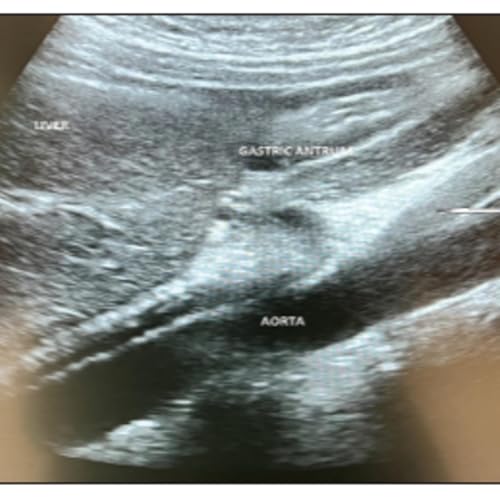

Featured paper: Preoperative gastric point‑of‑care ultrasound in nonelective surgical procedures in pediatric‑aged patients

What if a simple five-minute ultrasound could prevent a life-threatening complication during your child's emergency surgery? In this episode, we explore how point-of-care ultrasound (POCUS) is revolutionizing pediatric anesthesia by giving doctors a real-time window into the stomach before urgent procedures. Discover why traditional "nothing by mouth" rules aren't always enough when children are in pain or on opioids, factors that slow stomach emptying, and how gastric ultrasound measures the antrum to calculate exact aspiration risk. We dive into a real case where this technology caught unexpected solid food in a patient's stomach, preventing a dangerous induction, and explore how 98% of emergency pediatric patients turned out to be safe for controlled anesthesia instead of risky rapid-sequence intubation. Learn why seeing inside the stomach matters for children with neck injuries or difficult airways, and how this non-invasive tool is transforming surgery from guesswork into precision medicine. Join us for a reassuring look at how one simple scan is making emergency surgery safer for kids.